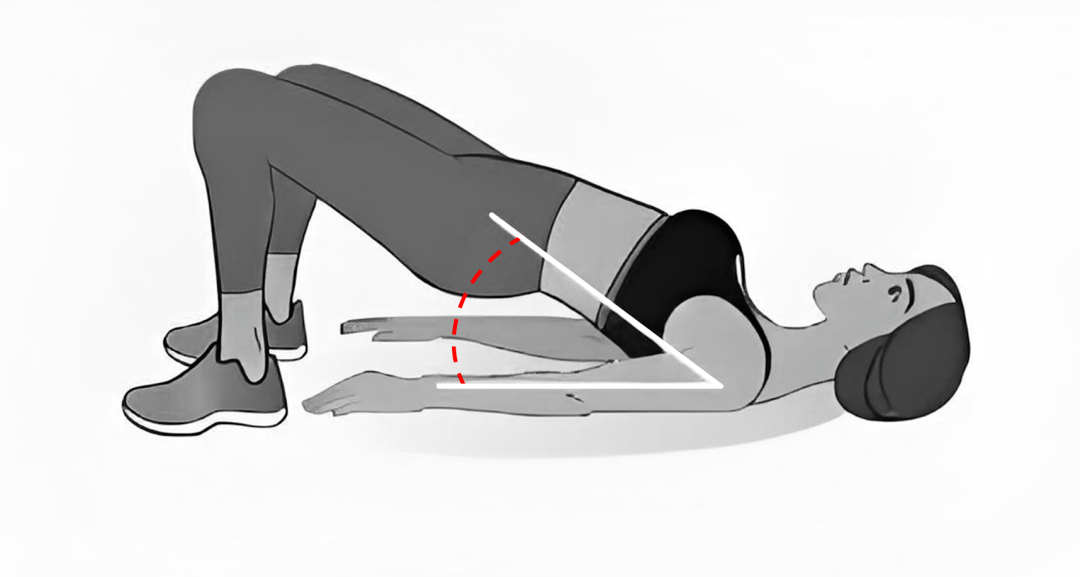

3.1周内练腰背肌:术后1周内,佩戴好腰围,在医生指导下做简单的腰背肌锻炼,比如五点支撑法——仰卧在床上,以头、双肘和双足跟为支撑点,缓缓抬起腰背部,保持几秒后再放下。要根据自己的体能量力而行,别过度用力。